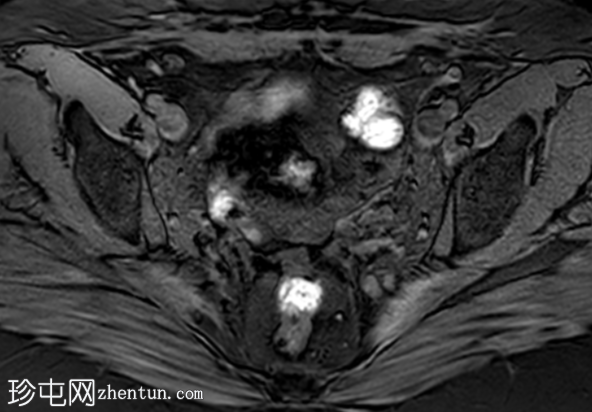

轴位T2加权像

脂肪抑制像

盆腔MRI显示左侧骶前区有两个小囊性病变,位于左侧附件的预期解剖位置。

病变在T2加权像上呈高信号,边界清晰,囊壁轻度增厚,光滑。在T1加权脂肪抑制像上,一个病变内部呈高信号,另一个病变呈低信号。静脉注射对比剂后,可见轻度周边囊壁强化,未见强化的实性成分。

未见扩散受限。病灶与邻近盆腔血管关系密切,无周围炎症改变、盆腔淋巴结肿大或游离液体的证据。